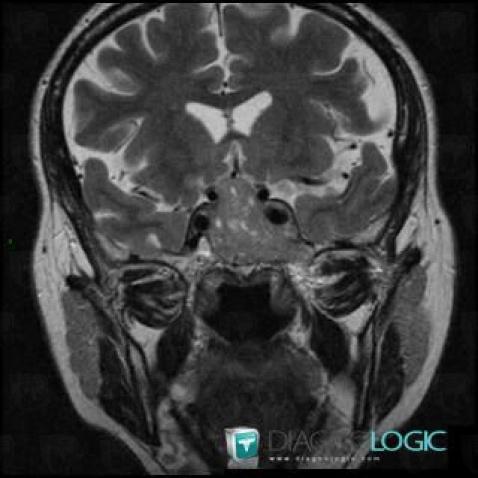

Macroadénome hypophysaire, Hypophyse et région parasellaire, IRM

Voici les informations spécifiques à l'image clé ci dessus:

- Diagnostic Macroadénome hypophysaire, Localisation(s) Hypophyse et région parasellaire, comportant les gammes Lésion du sinus caverneux